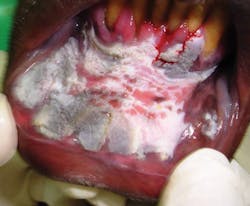

We may see patients who come to the United States from areas such as Sudan who have a history of toombak use, and this may go unrecognized. Without the correct knowledge of the product - that is particularly unfamiliar to western health-care providers - the changes in tissues may be disregarded. Some individuals may present with precancerous lesions, early cancer, or late stage disease during a visit to a private dental practice or dental school. Babiker, et al. presents a case for increasing our knowledge of the ramifications of such products on the oral tissues and early identification of tissue changes that early cases may still be effectively treated with reduced morbidity (see Figure 1).

In the local communities of Sudan, toombak is also called “saffa.” This is rolled up into a medium sized ball and usually placed in the anterior vestibule for two to three hours after which it is discarded and replaced (see Figures 3, 4). Toombak is a homemade product that is not quality regulated by the government of Sudan. Easy access and cheap sales of the product make it readily available for sale and personal use. Usage is widespread amongs all age groups (beginning as young as 10 years old) in both males and females. The product is placed in large containers that may be stored for an unlimited time and quite susceptible to other environmental contaminants. Raised temperatures lead to progressing fermentation, thus compounding its carcinogenic affect.

Toombak users are more susceptible to infections, inflammation of the oral tissues as well as premalignant lesions (dysplasia, keratinization, and hyperkeratosis). It is scientifically proven that toombak lesions display increased dyskeratosis, apoptosis is inhibited, and genetically the P53 tumour suppressor gene is downregulated. Thus, the development of lesions are much more likely to have an invasive nature with the ability to metastasize.